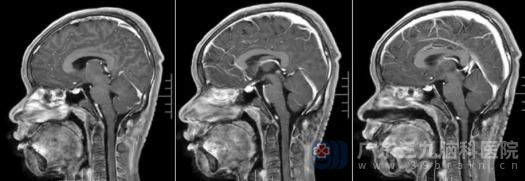

术后MR检查显示,原延髓颈髓交界区后方椎管内病变已成功切除。病理结果提示为符合神经管原肠囊肿(肠源性囊肿)。出院时,罗昊神志清醒,对答如流,四肢肌力恢复如初。

术后复查影像